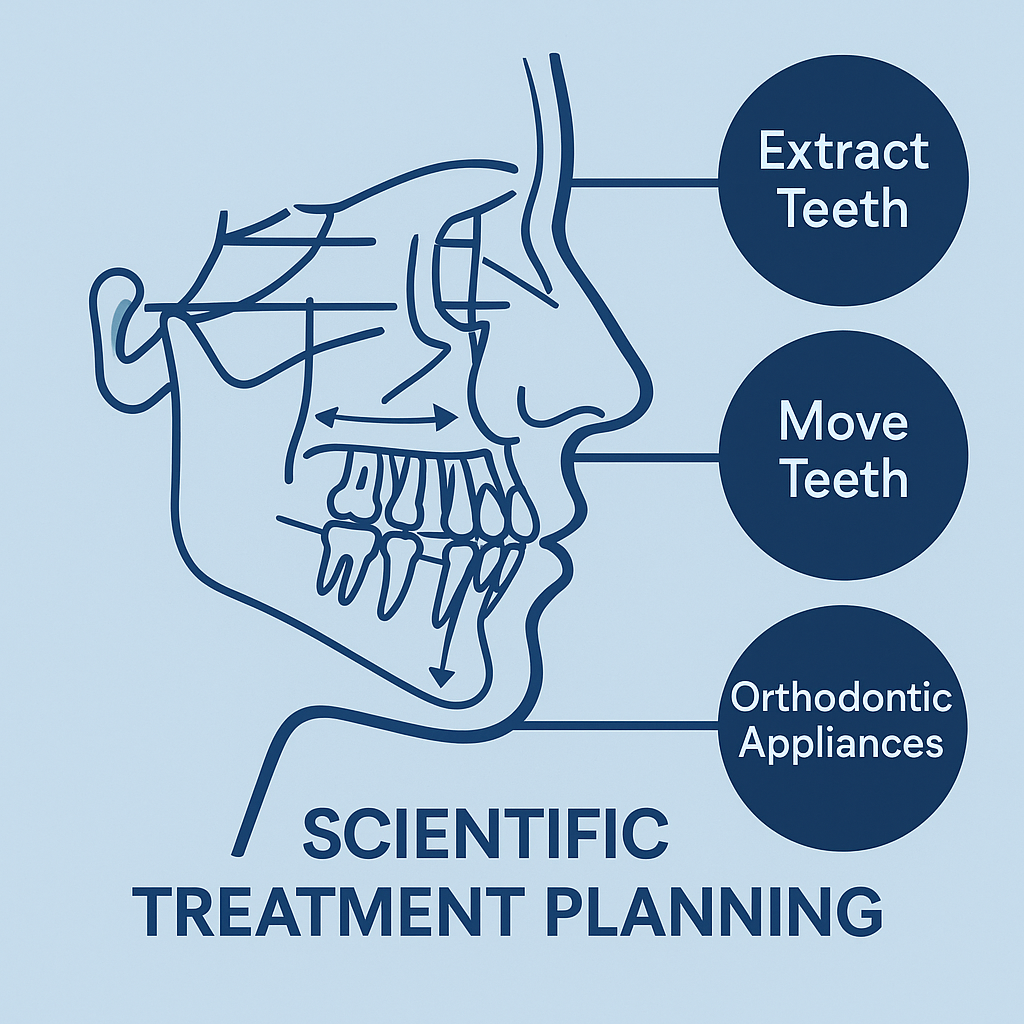

۲. طراحی طرح درمان کاملاً علمی و غیرحدسی

درمان ارتودنسی یک فرایند طولانیمدت است و کوچکترین اشتباه در تشخیص میتواند نتیجه نهایی را تحت تأثیر قرار دهد.

تحلیل سفالومتری به متخصص کمک میکند:

- نیاز به کشیدن یا نکشیدن دندان را مشخص کند.

- بداند کدام دندانها باید حرکت داده شوند و در چه جهتی.

- برنامهریزی کند که طول درمان تقریباً چقدر خواهد بود.

- تشخیص دهد که آیا فقط براکت کافی است یا باید با دستگاههای دیگر مثل هدگیر یا ارتوپدیک ترکیب شود.

به زبان ساده:

سفالومتری نقشه GPS درمان ارتودنسی است؛ بدون آن ممکن است نتیجه غیرقابل پیشبینی یا غیرقابل بازگشت ایجاد شود.